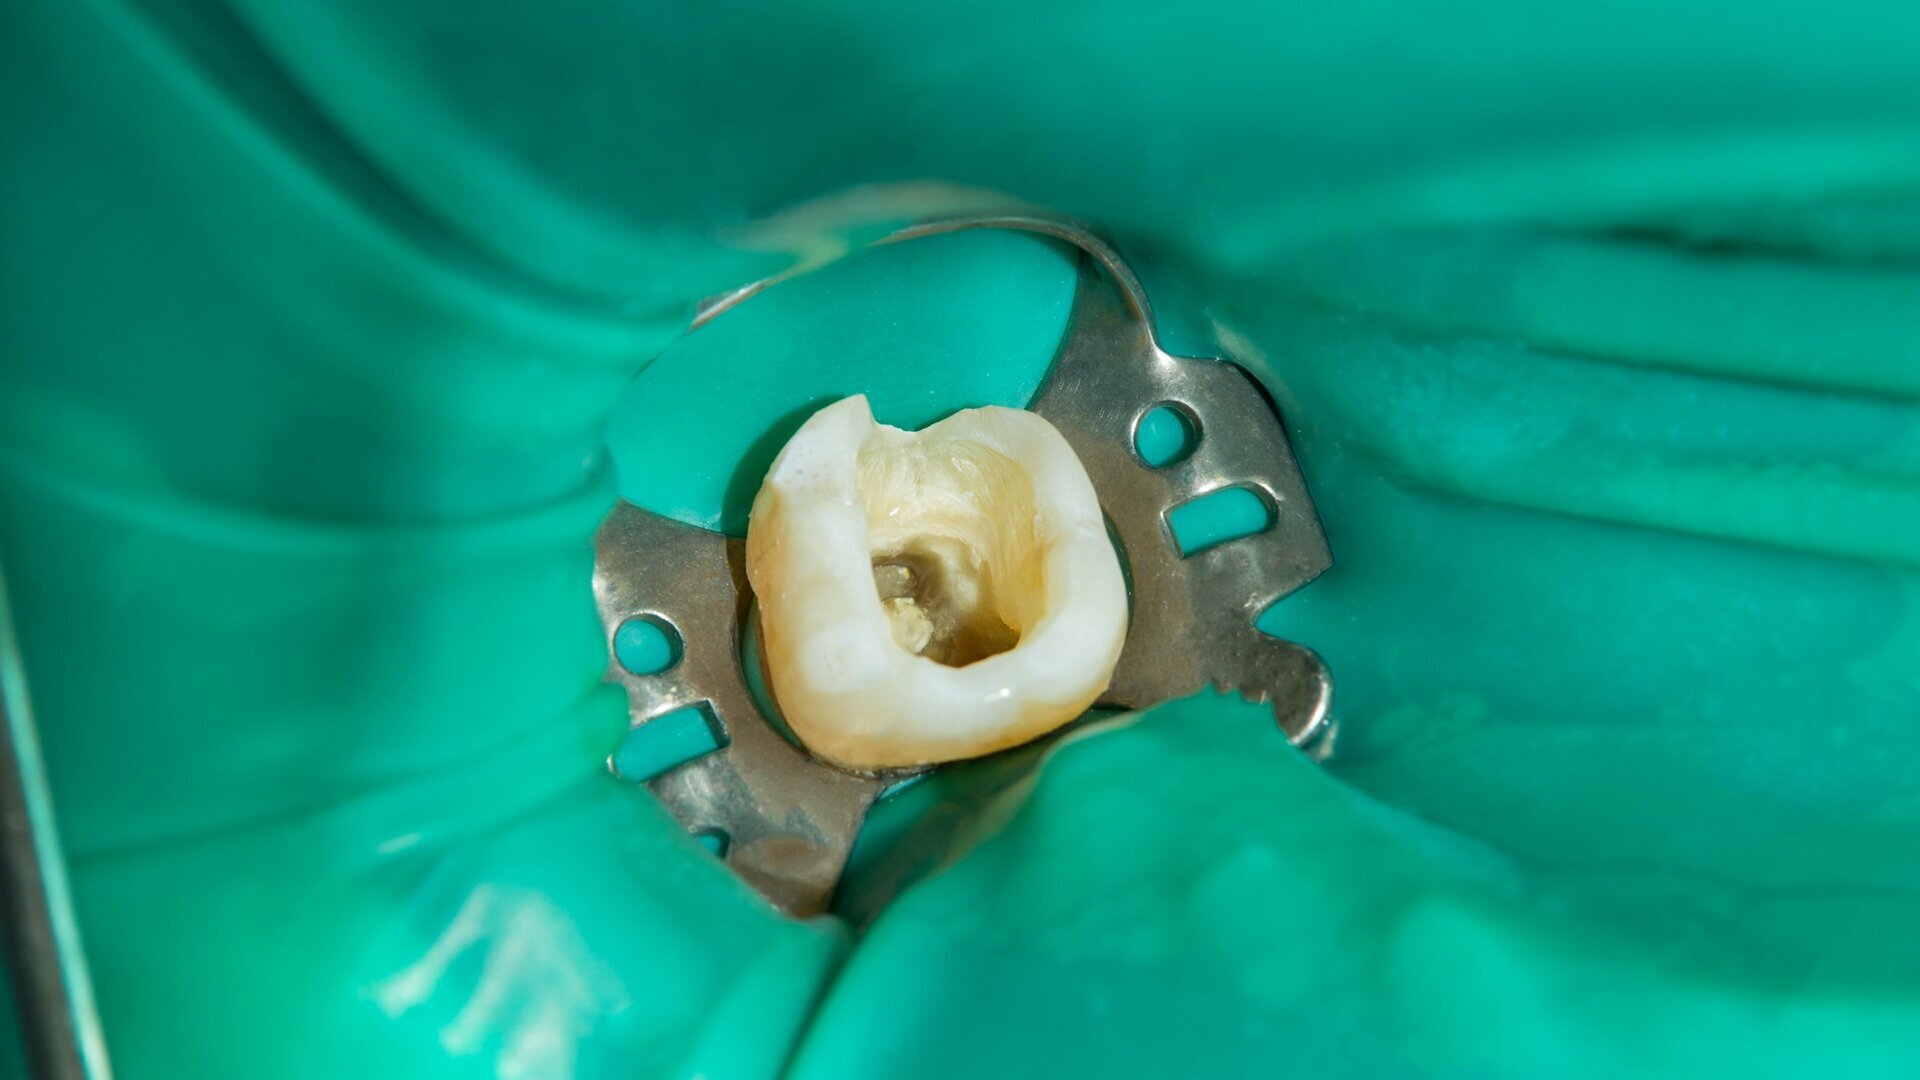

Endodoncija je postupak uklanjanja infekcije i oštećenog tkiva iz kanala korena, čime se čuva prirodan zub i sprečava dalje oštećenje. Tretman je precizan, bezbolan i efikasan, a za najbolje rezultate koristimo moderne tehnologije i savremene metode lečenja.

Koferdam je zaštitna gumena opna koja izoluje zub tokom tretmana. Omogućava suvo i čisto radno polje, povećava preciznost lečenja i štiti pacijenta od neprijatnosti, čineći postupak bezbednijim i efikasnijim.